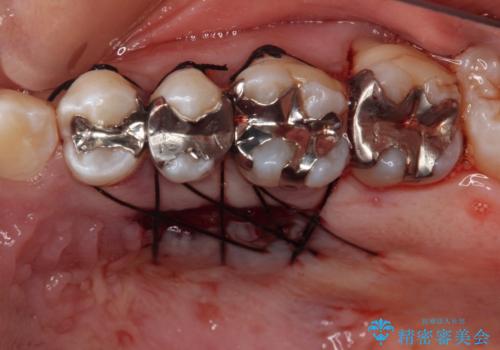

歯肉退縮に対して、上顎からの結合組織移植術(CTG)により、歯根の被覆を行うとともに、歯肉の厚みを増すことで将来の退縮リスクを抑制することとしました。

上顎両側から歯肉を採取したたため、術後は痛みや出血で辛い思いをされましたが、1回の処置で満足のいく結果となりました。